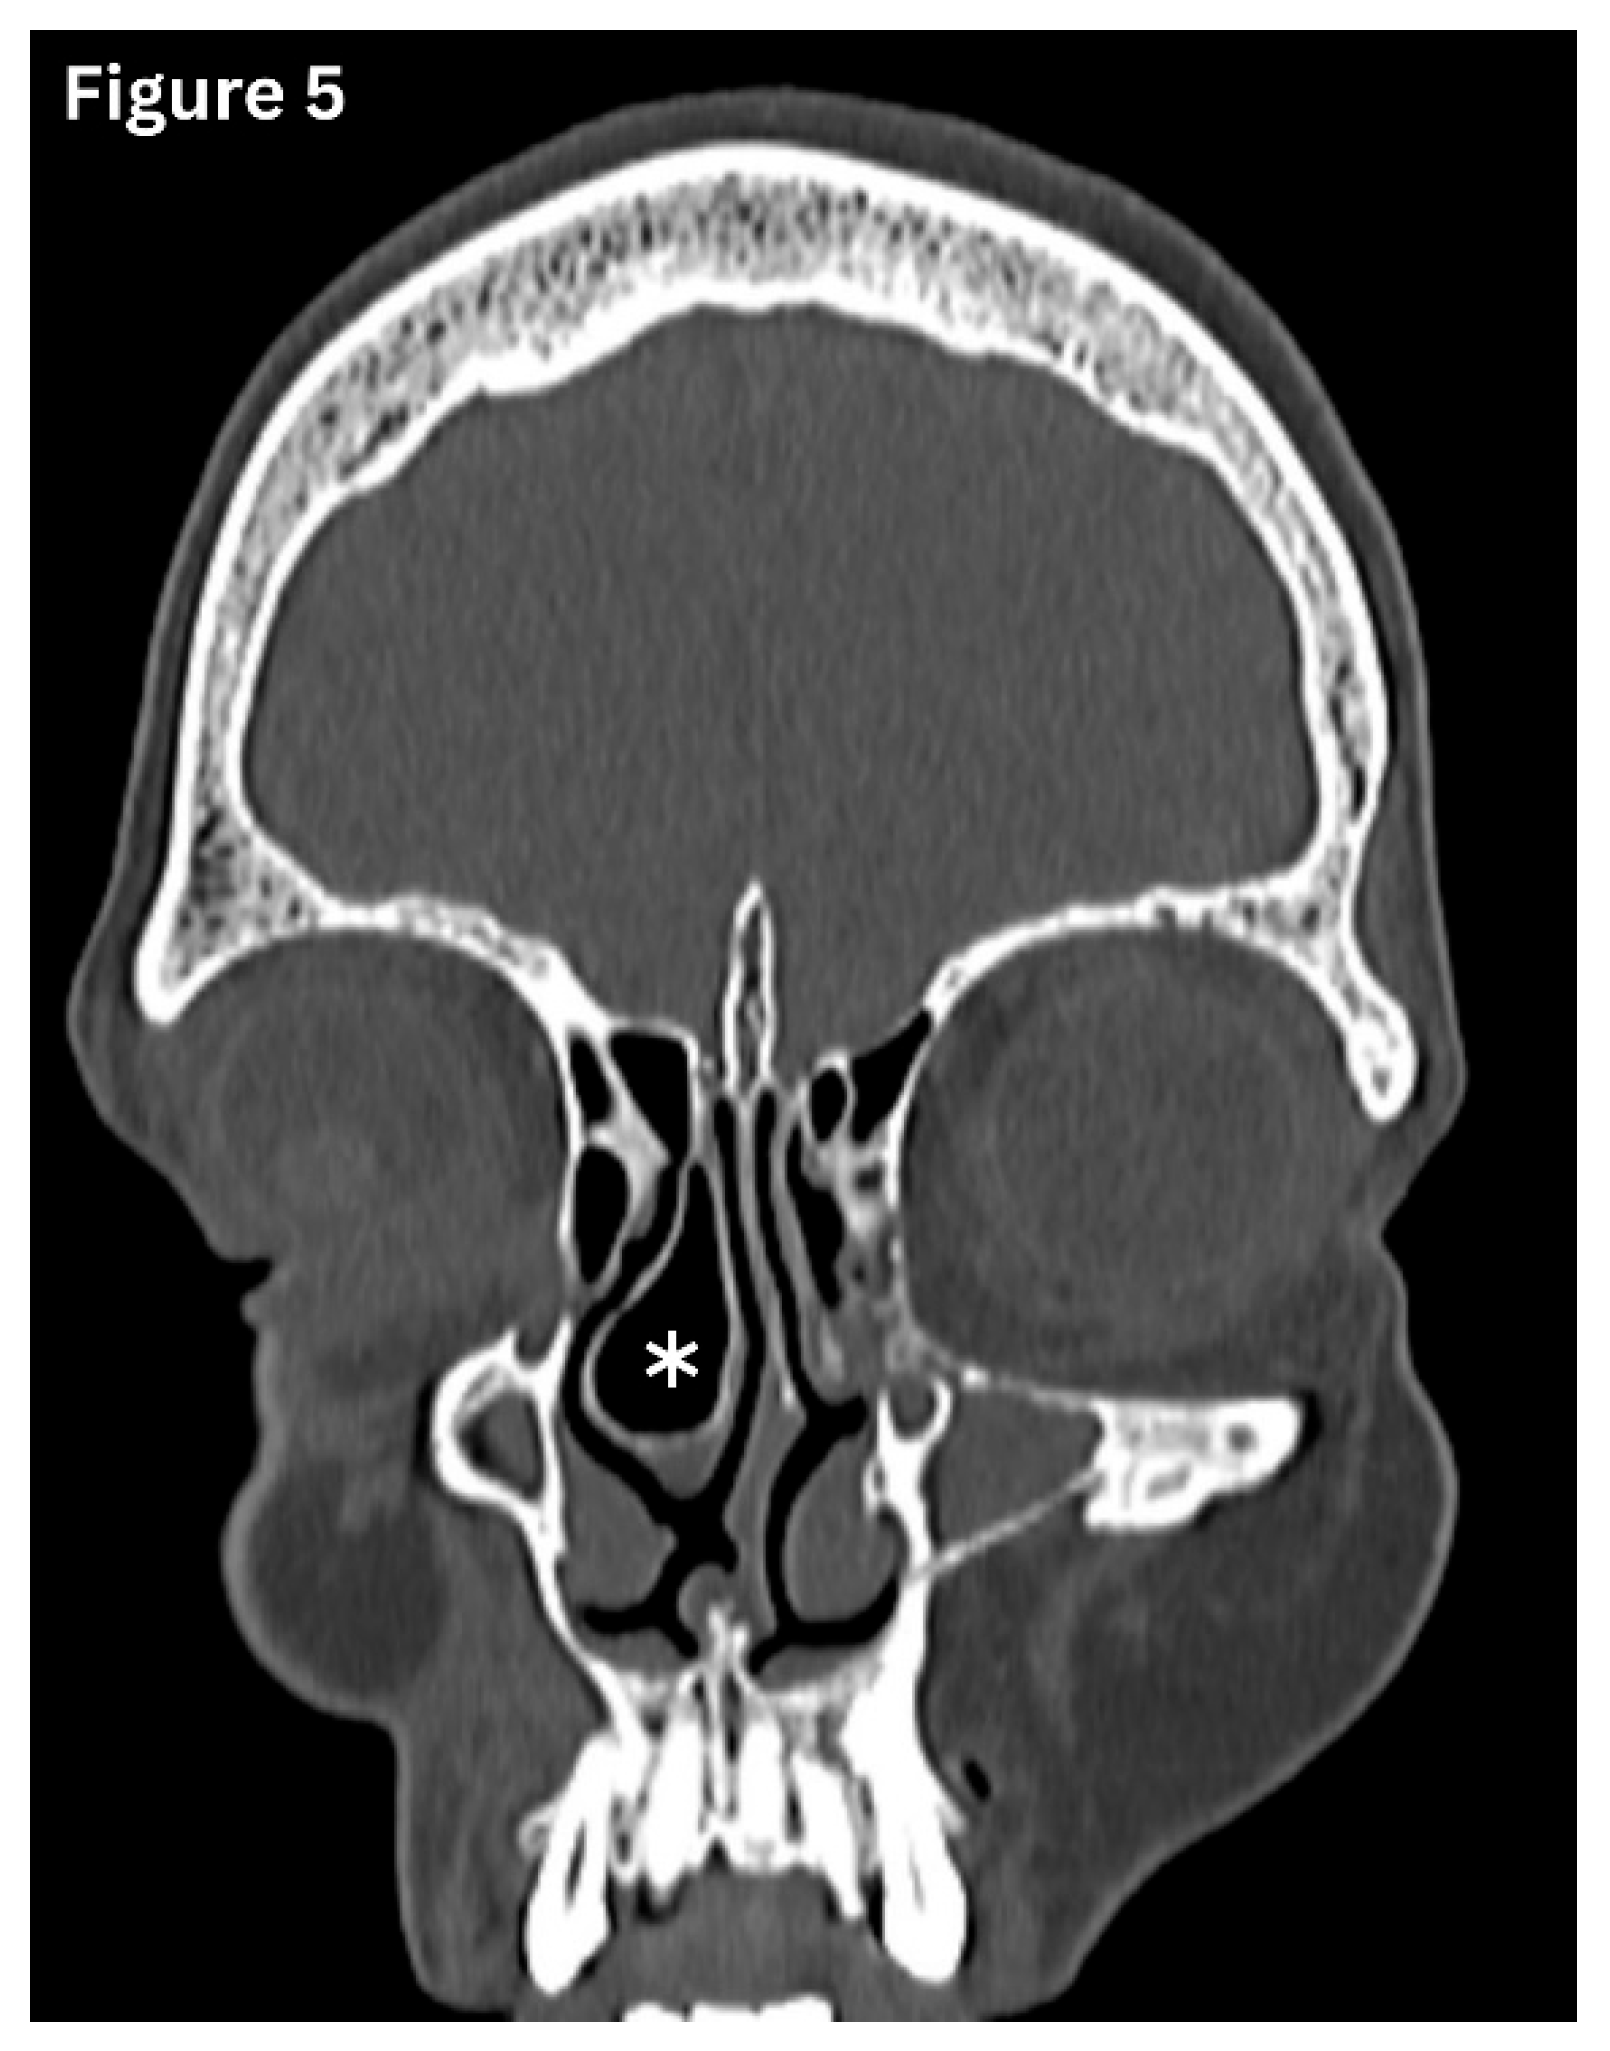

Concha Bullosa (CB)

This refers to a pneumatised vertical part of the middle turbinate. (Figure 5) Concha Bullosa is observed in approximately 24–55% of individuals and is most commonly present on both sides of the nose [11]. This variation may compress the OMC, leading to nasal obstruction or recurrent rhinosinus infections.

Figure 5. Coronal CT image shows pneumatization of the right middle turbinate-conchabullosa.